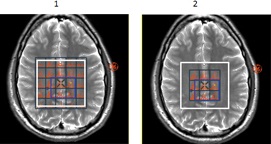

Figure 4. Spectra in voxel display

Table 2. Image legend Number Description 1 Show all voxel inside PRESS Box is selected and therefore displays spectra within all voxels in the PRESS Box. 2 Show all voxel inside PRESS Box is not selected and therefore only spectra within the deposited ROI appear.